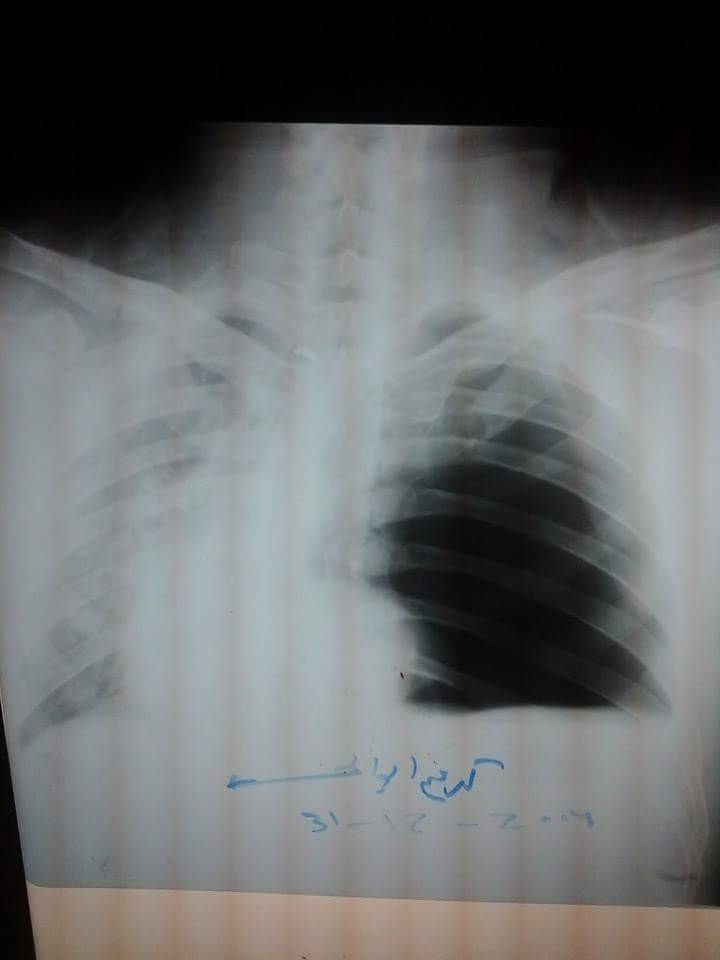

A 45-year-old man came to the emergency department complaining of progressive shortness of breath for 10 days. He also complained of vomiting and absolute constipation for four days. He had a past history of left stab to the chest for 1.5 years. Examination revealed the patient was hemodynamically unstable, with severe respiratory distress, cyanosis, fever, and absent air entry on the left side of the chest. The patient had a chest x-ray suggestive of tension pneumothorax, however a chest computed tomography scan was suggestive of diaphragmatic hernia.